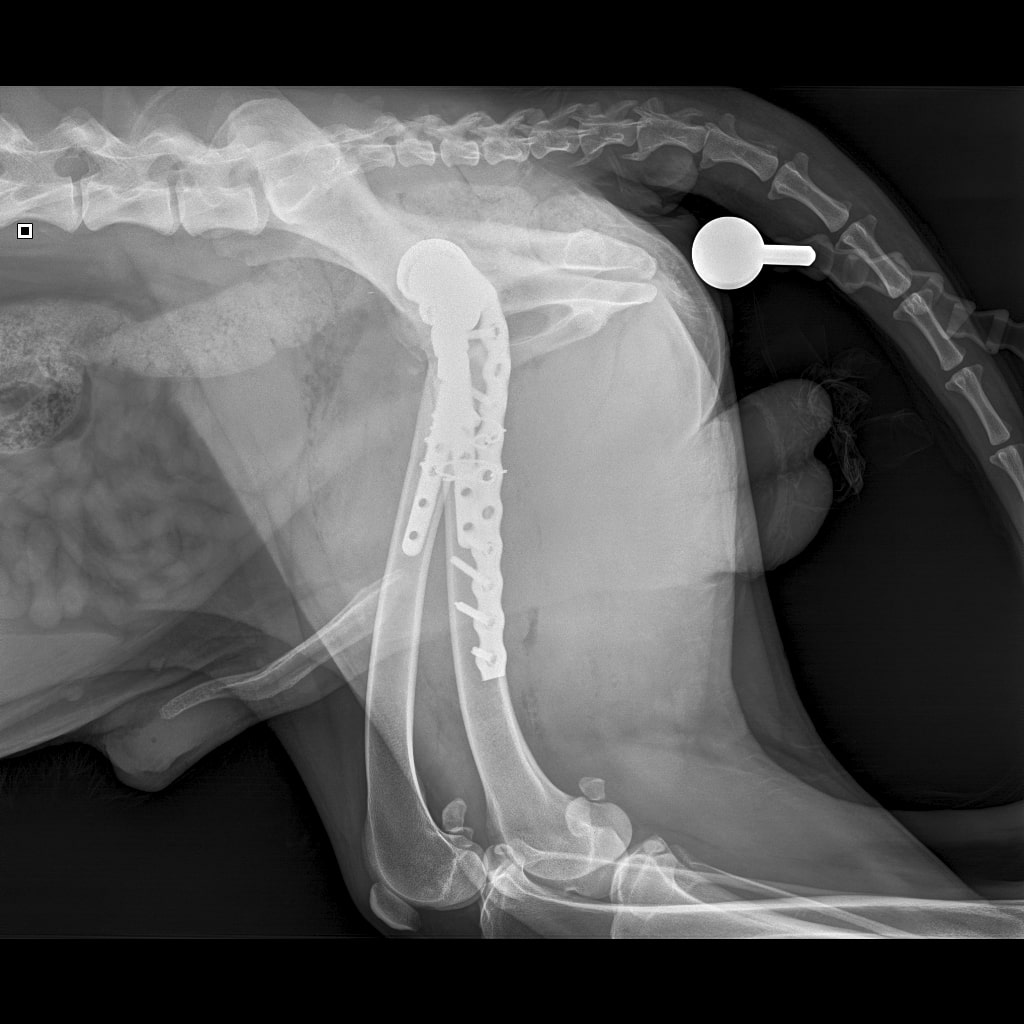

8A836050-66CA-42B2-94D3-F13B288A592B.jpeg

39B2671E-39B9-4502-9E11-ADB169612F24.jpeg

6950B9C9-79EA-4F34-A780-9C3C6BA31B49.jpeg

58C20B18-AA4E-4386-BF83-56CE5E282844.jpeg

Наш металлический мальчик

Железный дровосек